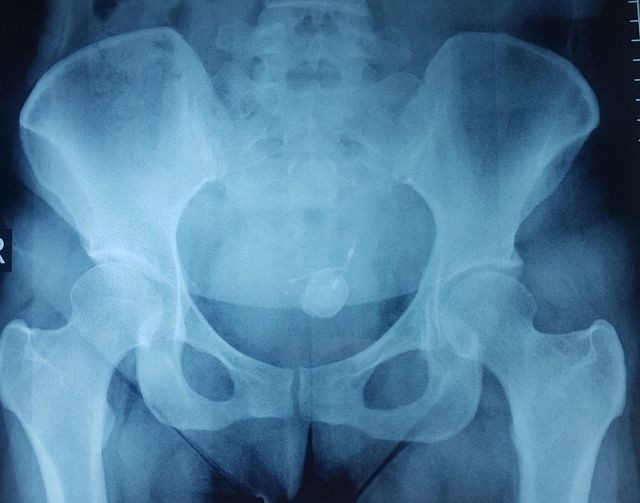

Một phần vòng tránh thai "hóa sỏi" cản quang trên hình ảnh kiểm tra

Qua thăm khám, chẩn đoán hình ảnh, bác sĩ phát hiện bàng quang của bệnh nhân có một vật thể lạ hình chữ T đã bị đóng sỏi, kích thước hơn 2cm. Một nhánh chữ T đã đâm xuyên thành bàng quang, phần còn lại T nằm trong ổ bụng. “Thủ phạm” được xác định là chiếc vòng tránh thai đã đẩy xuyên cổ tử cung chui vào ổ bụng rồi đâm vào bàng quang gây ra sỏi bàng quang.

Việc vòng tránh thai rơi ra ngoài hay vào ổ bụng thường gây ảnh hưởng nhiều đến sức khỏe. Trường hợp vòng di chuyển đến bàng quang rất hiếm. Bệnh nhân này một nhánh vòng tránh thai đâm xuyên thành bàng quang và giữ lại tại đó. Qua nhiều năm đã hình thành sỏi trong bàng quang gây các rối loạn đường tiết niệu.